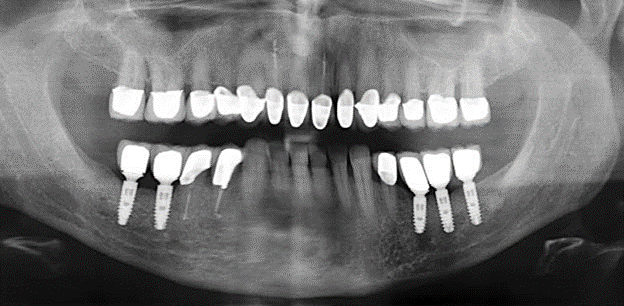

Eine 52-jährige Patientin stellte sich nach Zahnverlust im 3. Quadranten erstmals 2004 vor. Sie hatte den Wunsch nach einer prothetischen Neuversorgung. Im Rahmen der parodontologischen und radiologischen Diagnostik zeigte sich ein ausgeprägter parodontologischer Behandlungsbedarf. Die Zähne 48, 28, 27 zeigten zudem eine infauste Prognose und wurden entfernt (Abb. 1). Nach der erfolgreich abgeschlossenen systematischen PARTherapie wurde eine festsitzende implantatprothetische Versorgung mit Insertion von fünf Implantaten in Regio 35, 36, 37 und 46, 47 durchgeführt. Die prothetische Versorgung der natürlichen Zähne erfolgte mit verblendeten Zirkonoxidkeramikkronen, die Implantate wurden mit zweiteiligen individuellen Zirkonoxidabutments und ebenfalls verblendeten Kronen aus einer Zirkonoxidkeramik versorgt (Cercon base colored, Dentsply Sirona Lab). Die definitive Insertion der prothetischen Versorgung erfolgte im Jahr 2005.

Aufgrund der bestehenden parodontalen Vorerkrankung erfolgte die unterstützende Parodontaltherapie (UPT) in den ersten Jahren in einem DreiMonatsIntervall. Dabei zeigte die Patientin eine hohe Motivation und gute Compliance. Bei den jährlich erhobenen Sondierungsbefunden zeigten sich stabile parodontale Verhältnisse mit einem BOPIndex unter fünf Prozent. Aufgrund der stabilen parodontalen Situation und der guten Mitarbeit der Patientin wurde ab dem sechsten Jahr der prothetischen Funktionsphase das Recallintervall auf halbjährlich umgestellt. Auch mit diesem veränderten Recallintervall zeigten sich bei der jeweils jährlichen Aufnahme des Parodontalstatus stabile parodontale Verhältnisse, ohne Zunahme der Sondierungstiefen und einem BOPIndex unter fünf Prozent (Abb. 2a und b).

Im Rahmen der ZehnJahresKontrolle zeigten sich keine Hinweise auf einen fortschreitenden parodontalen Attachmentverlust oder einen periimplantären Knochenverlust (Abb. 3).